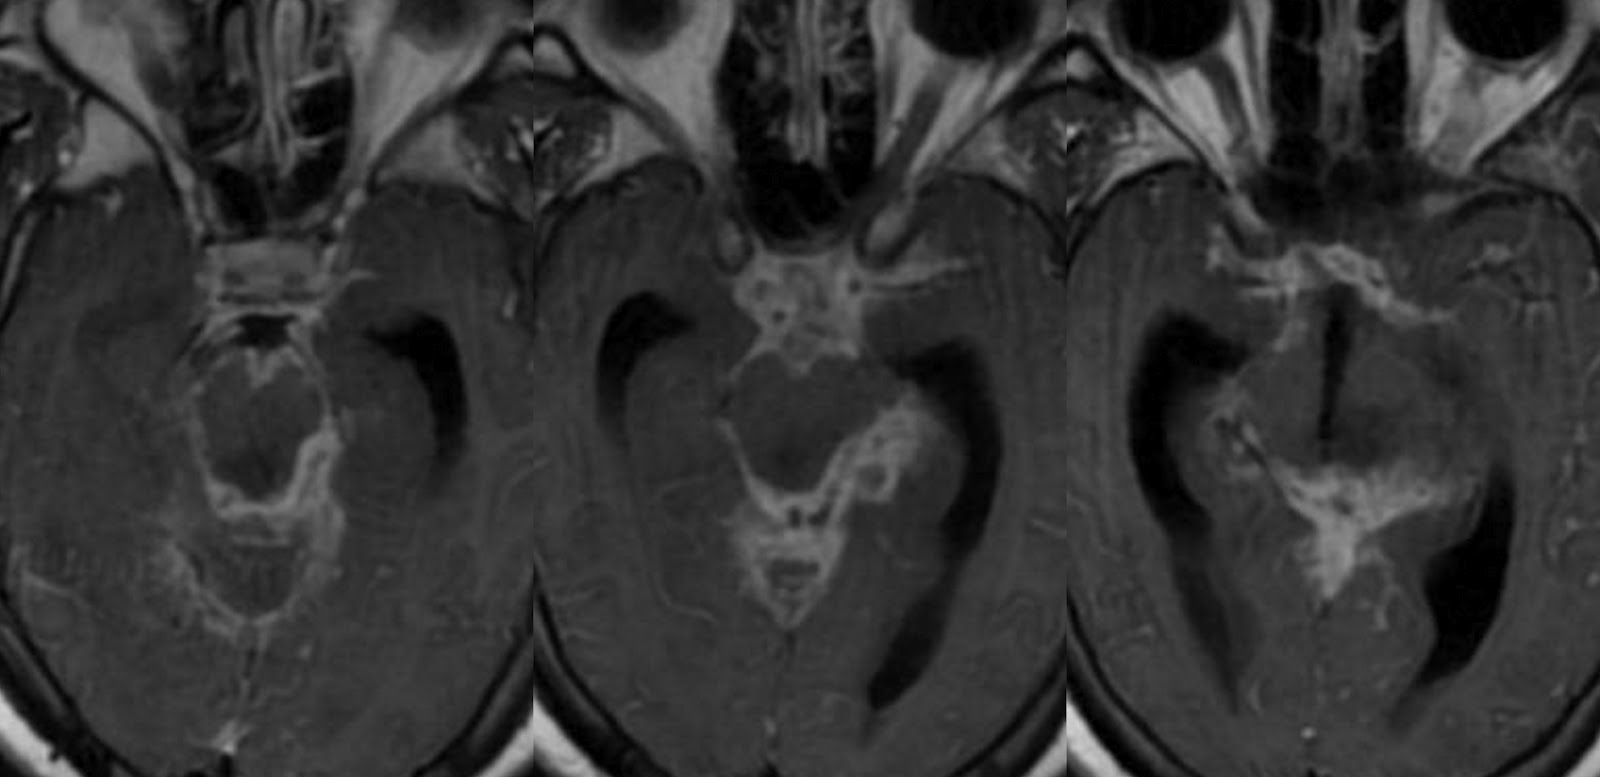

Meningeal tuberculosis. (a) Axial postcontrast brain CT shows typical Gelatinous Exudate Covering Base Of Brain Macroscopic view showing diffuse gelatinous exudates on the basal surface of the brain including the prepontine cistern, basal cistern, and bilateral sylvian fissures, and serious. Macroscopically there is a typically nodular, gelatinous exudate more pronounced in the sylvian fissures and over the base of the brain (. Tb basal arachnoiditis can form a thick gelatinous exudate around the base of. Gelatinous Exudate Covering Base Of Brain.

Dr Balaji Anvekar FRCR Basal exudates in Tuberculous meningitis Gelatinous Exudate Covering Base Of Brain Tb basal arachnoiditis can form a thick gelatinous exudate around the base of the brain and the cranial nerves leading to. The hallmark pathological feature of tbm is a thick gelatinous exudate, dominantly present at basal parts of the brain. With meningeal involvement, a grayish, mucinous exudate accumulates over the involved brain surface. Macroscopically there is a typically nodular, gelatinous. Gelatinous Exudate Covering Base Of Brain.

Contrastenhanced MRI brain showing enhancing basal exudates in the Gelatinous Exudate Covering Base Of Brain Macroscopic view showing diffuse gelatinous exudates on the basal surface of the brain including the prepontine cistern, basal cistern, and bilateral sylvian fissures, and serious. Tb basal arachnoiditis can form a thick gelatinous exudate around the base of the brain and the cranial nerves leading to. Macroscopically there is a typically nodular, gelatinous exudate more pronounced in the sylvian fissures. Gelatinous Exudate Covering Base Of Brain.

Fig. 6.5, [Proven tuberculous meningitis with multiple...]. Diseases Gelatinous Exudate Covering Base Of Brain The hallmark pathological feature of tbm is a thick gelatinous exudate, dominantly present at basal parts of the brain. Tb basal arachnoiditis can form a thick gelatinous exudate around the base of the brain and the cranial nerves leading to. Macroscopic view showing diffuse gelatinous exudates on the basal surface of the brain including the prepontine cistern, basal cistern, and. Gelatinous Exudate Covering Base Of Brain.

Dr Balaji Anvekar FRCR Basal exudates in Tuberculous meningitis Gelatinous Exudate Covering Base Of Brain With meningeal involvement, a grayish, mucinous exudate accumulates over the involved brain surface. Macroscopic view showing diffuse gelatinous exudates on the basal surface of the brain including the prepontine cistern, basal cistern, and bilateral sylvian fissures, and serious. Macroscopically there is a typically nodular, gelatinous exudate more pronounced in the sylvian fissures and over the base of the brain (.. Gelatinous Exudate Covering Base Of Brain.